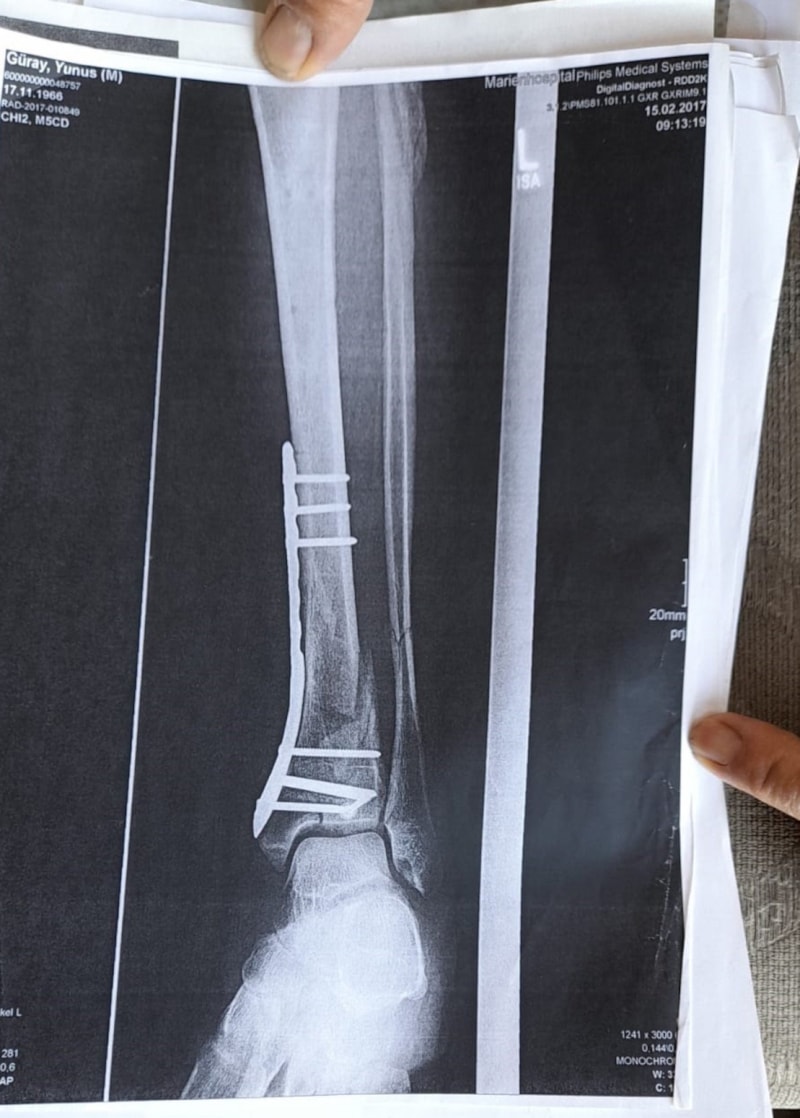

Antalya 4’üncü İdare Mahkemesi’ndeki dava dosyasında, Almanya’dan 31 Aralık 2016 günü Antalya’ya gelen ve 1 Ocak 2017 günü saat 00.30 sıralarında Cumhuriyet Meydanı’ndaki kutlamaları izlemek isteyen Yunus Güray’ın, 2 metrelik çukura düştüğü ve ayağından ciddi şekilde yaralandığı belirtildi.

Müze Müdürlüğü sorumluluğundaki sondaj çukuruna düşerek yaralanması sonucu 6 ameliyat geçiren Yunus Güray adına açılan tazminat davasında, toplam 1 milyon 50 bin TL’lik maddi tazminatın olay tarihinden itibaren yasal faiziyle ödenmesi talep edildi.

Olay yeriyle ilgili fotoğraf ve görüntüleri mahkemeye sunduklarını kaydeden Güray, “Ömrümü yediler, demir var ayağımda, sakat bıraktılar. Ayağı keseceklerdi neredeyse. Şu an kalıcı sakatlık var. 1 sene kendime gelemedim, 2 haftada bir ameliyata giriyordum. Almanya’da 3 ay hastanede kaldım ve ayağımda yüzde 3’lük engel oluştu” diye konuştu.